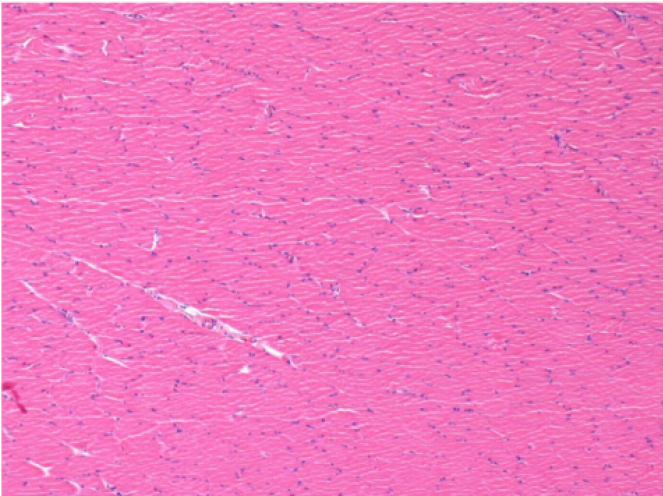

3 months after Endopeel Injection

3 months (D90)after Endopeel Injection 0.1ml in the right pretibial muscle.

L : Control-100xD90

R:100xD90